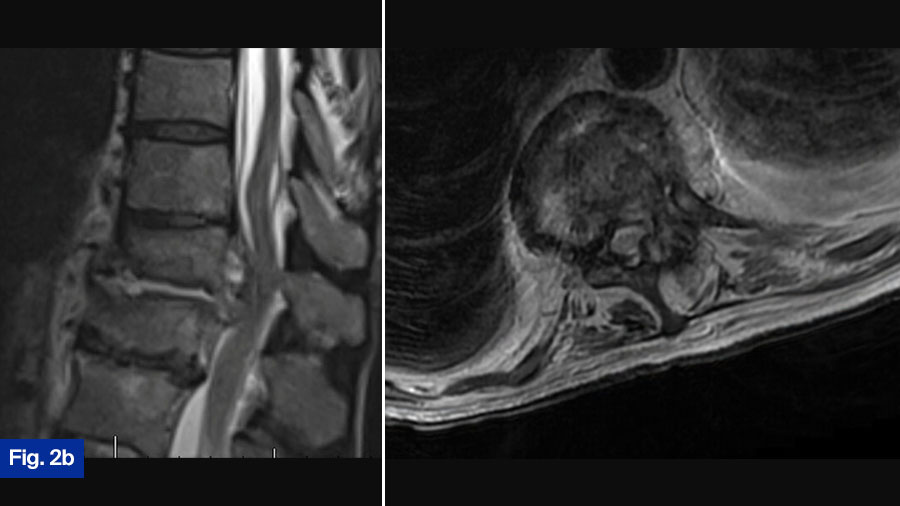

- CT scan: Demonstrated bony destruction and increased segmental kyphosis at T11-T12 (Figure 2a).

- MRI scan: Demonstrated a large ventral epidural phlegmon with moderate cord compression and thoracic hyperintensity with end-plate destruction (Figure 2b).

- Upright radiographs: Further evaluated spinal stability (Figure 2c).

This patient is the most controversial case. The patient is neurologically intact but has spinal cord compression from an infection. Furthermore, this patient has significant bony erosions. I would treat this patient with surgical intervention in an urgent manner. Significant infection around the spinal cord can cause a spinal cord injury from a mechanical mechanism, but it can also cause vasospasm and spinal infarction. When looking at cervical epidural abscess, Alton et al (TSJ 2015) found a 75% failure rate of medical management largely due to a progressive neurologic deficit. While undoubtably there is some difference between the thoracic and cervical spine, I treat all patients with significant spinal cord compression from an infection surgically. At my institution, this patient would routinely have a lateral partial corpectomy utilizing autologous iliac crest autograft, followed by an instrumented posterior decompression and fusion, The patient would routinely get 6 weeks of IV antibiotics, however the use of suppressive antibiotics after the completion of IV is often variable. While there can be significant debate about the best surgical treatment, I think this patient should undergo surgical intervention.

This case is certainly controversial. At my institution, when such a case is presented at rounds, the room is divided regarding best treatment (initial medical treatment versus initial surgical treatment). Interesting and lively debates occur. This patient presents with a new diagnosis of discitis/osteomyelitis with some bony destruction and epidural abscess. He is neurologically intact and upright radiograph show the segment to be stable. Given this, I would admit the patient and attempt initial medical management. I would monitor response to treatment clinically as well as via laboratory inflammatory markers. Often, in the context of infection that receives adequate medical treatment, we see fusion of the segment. However, this patient will need to be monitored closely once discharged from the hospital with regular clinical assessments with upright radiographs as well as close monitoring by the infectious disease team. It is still possible that this patient requires surgical intervention. Given the growing international academic interest in this disease and the possible growing evidence that initial surgical intervention is best, it is possible that my approach to these types of cases will change as we reach consensus on best treatment.